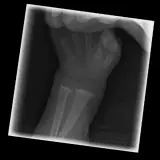

MSK Radiographs